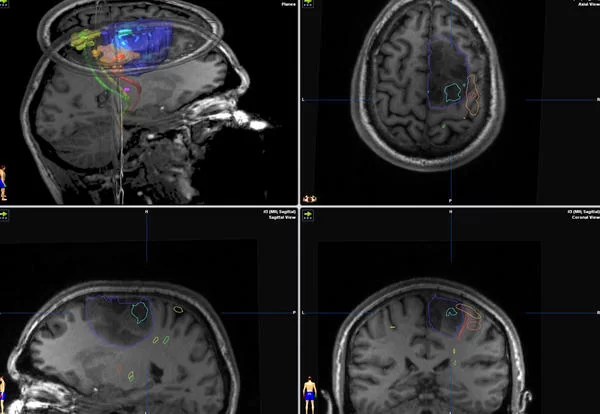

Ο νευροχειρουργός μπορεί να καθοδηγείται από μαγνητική τομογραφία στο χειρουργείο (“διεγχειρητική μαγνητική τομογραφία”) ή από μια ειδική βαφή που βοηθά στην εξέταση του όγκου υπό το μικροσκόπιο κατά τη διάρκεια της χειρουργικής επέμβασης (τεχνική 5-ALA, εικόνα 1). Μερικές φορές ο νευροχειρουργός μπορεί να συστήσει μια “λειτουργική” MRI εγκεφάλου (functional MRI) πριν από την επέμβαση, προκειμένω να καταλάβει καλύτερα που βρίσκονται οι διαφορετικές νευρολογικές λειτουργίες (ομιλία, κίνηση) στον εγκέφαλό (εικονα 2).